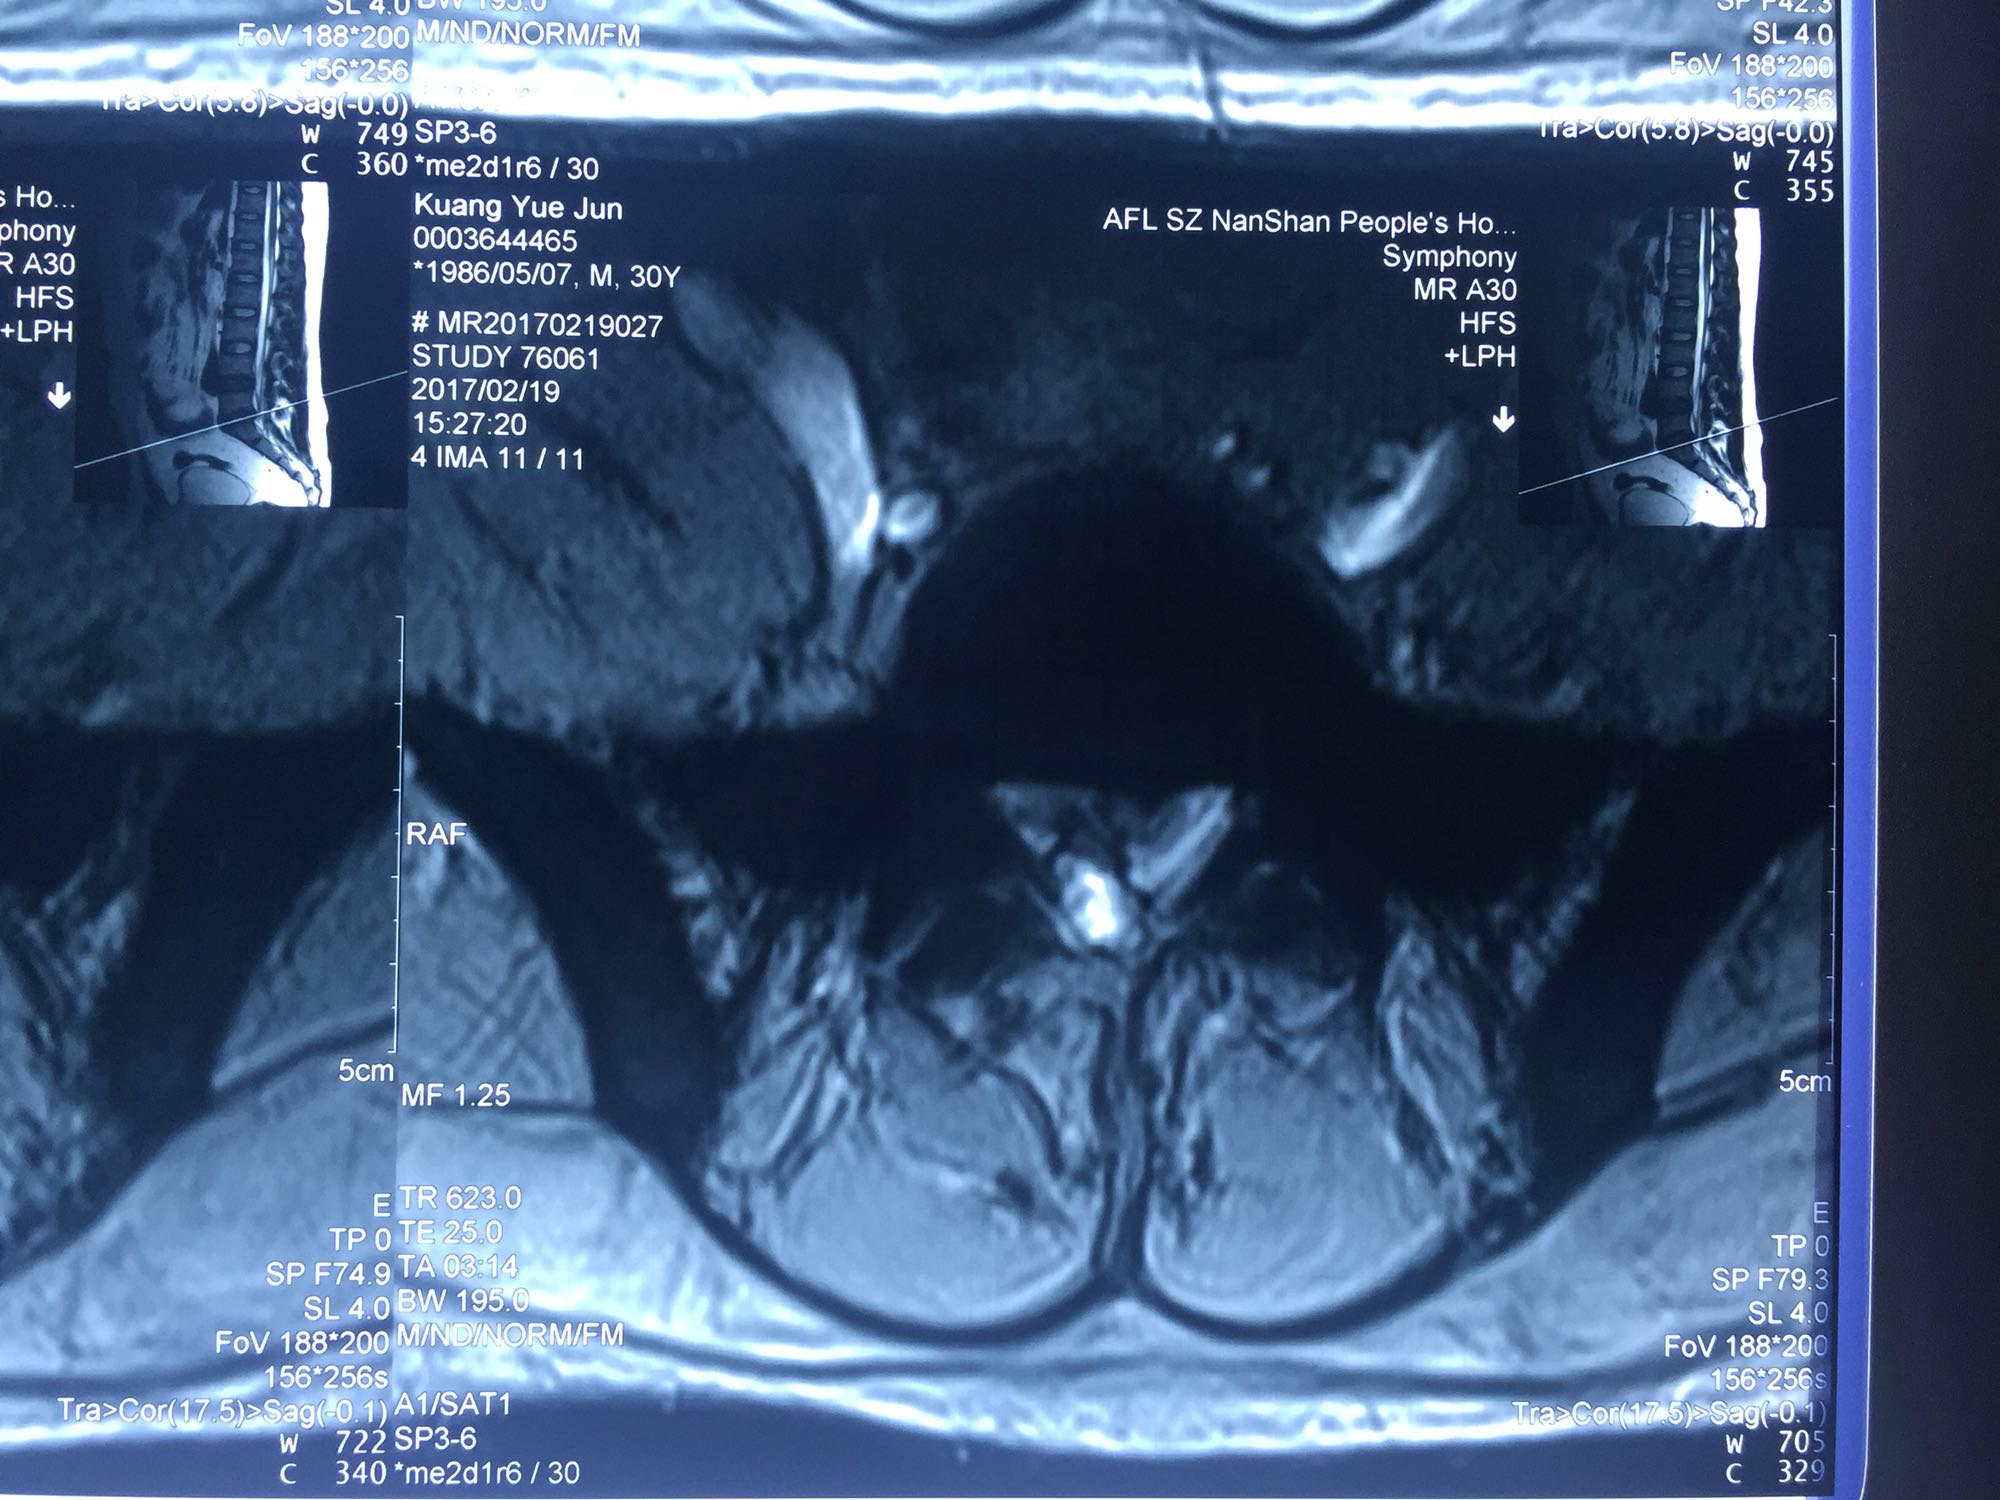

腰椎间盘脱出

邝X军,男性,30岁,因左下肢疼痛1天而入院。 1天前无明显诱因出现左下肢疼痛,程度较重,难以忍受,伴有行走困难。

腰骶部肌紧张,腰5骶1棘间及左侧椎旁有压痛及放散痛,左侧坐骨神经出孔处有压痛及放散痛,左侧足背外侧及足底部皮肤感觉麻木,左侧直腿抬高试验阳性(30度)。

诊断:腰5骶1椎间盘突出症 治疗方案:椎间孔镜下经椎板间入路髓核摘除术